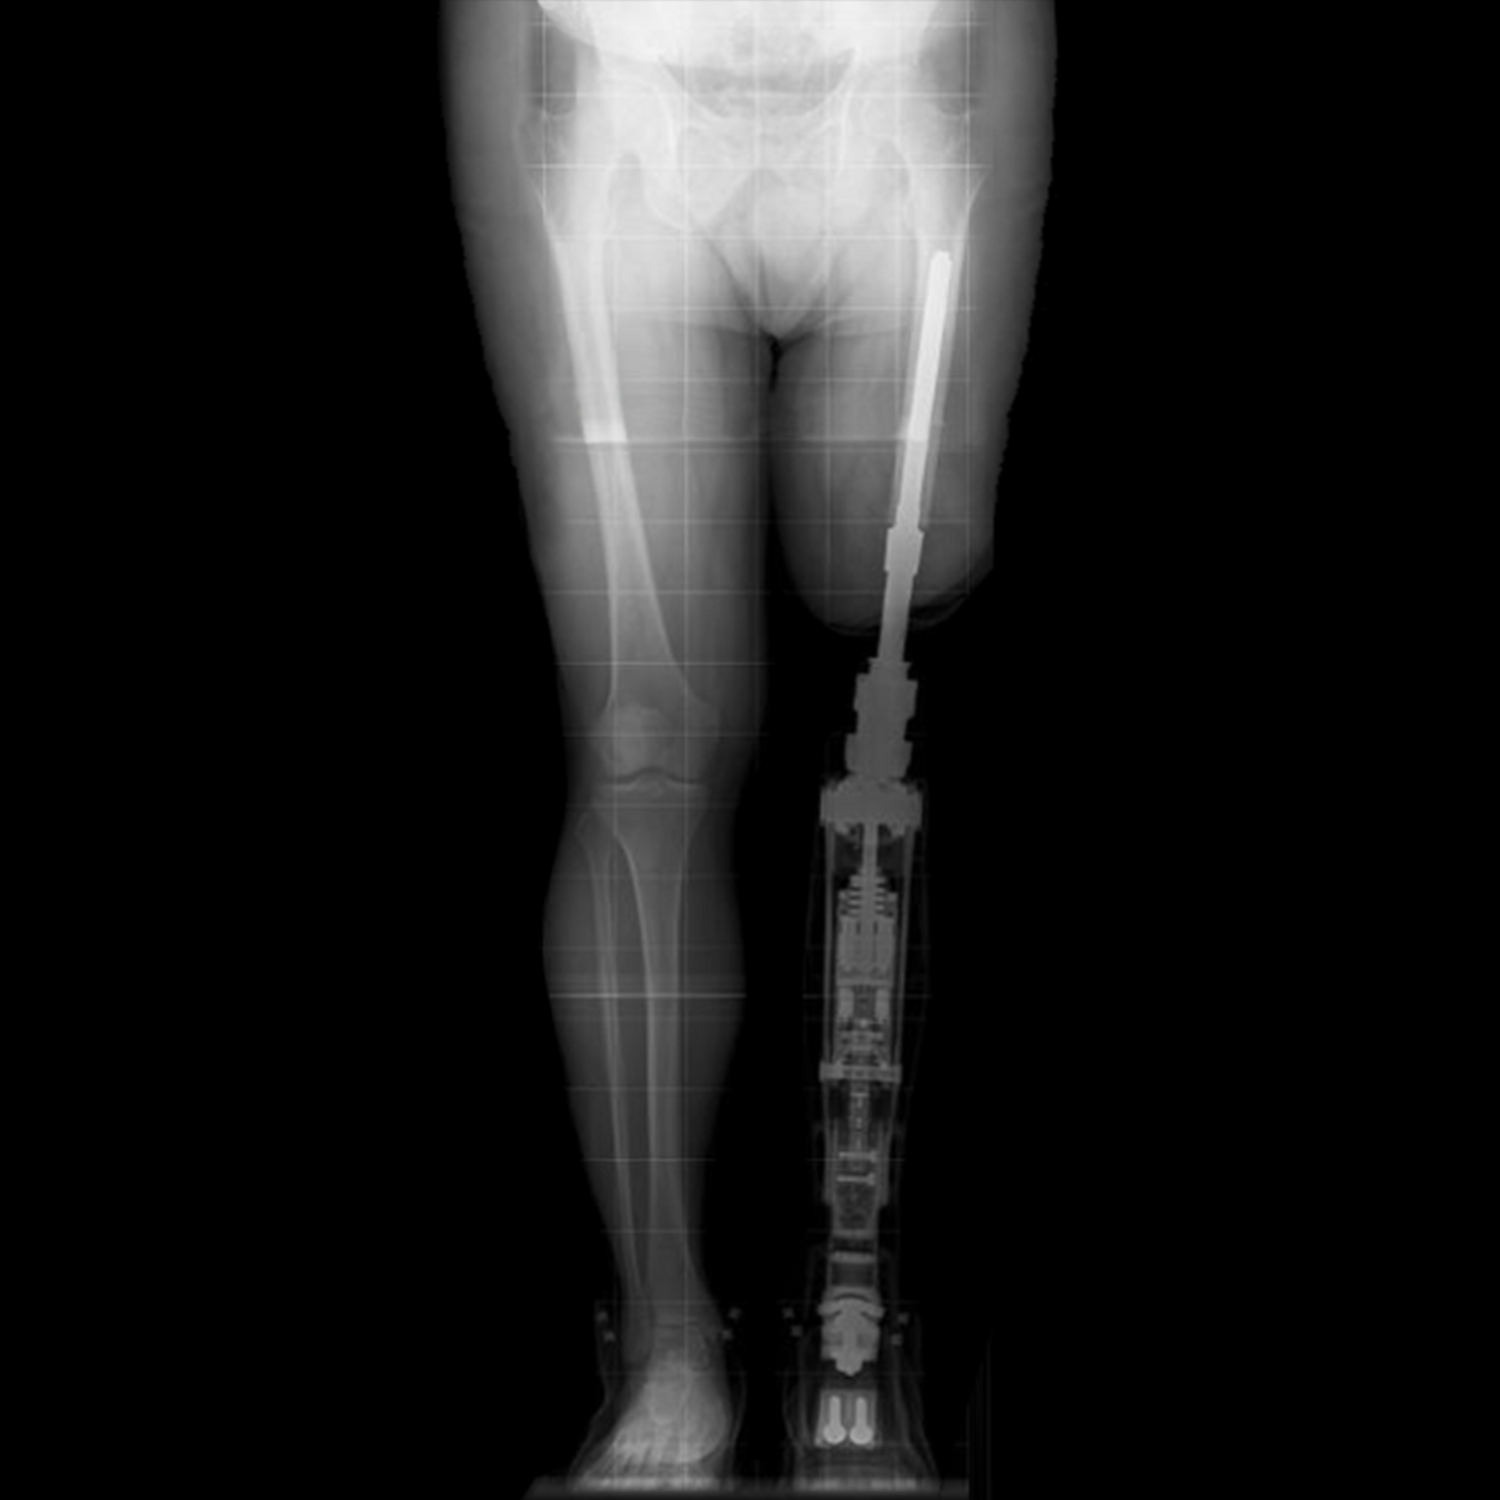

Osseointegration is a surgical technique that has revolutionised the way amputees can use prosthetic limbs. The procedure involves the insertion of a titanium metal implant directly into the bone, which allows for a secure and stable attachment of the prosthetic limb. This results in improved mobility, reduced pain and discomfort, and a greater sense of independence.....

Osseointegration eliminates the need for a traditional socket to attach a prosthetic limb to the residual limb. The prosthetic limb is attached directly to the implant, which provides a more secure and comfortable fit.

Limblink™ is the proud distributor of the BADAL X™ system by OTN Implants in New Zealand.